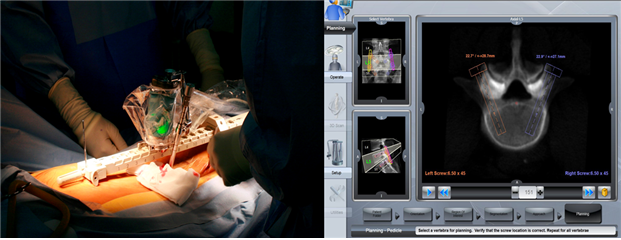

척추 로봇수술은 ‘척추 유합술’에 주로 사용되는데, 신경을 누르고 있는 뼈, 인대, 디스크 등을 제거한 후 빈 공간에 케이지(고정물)를 삽입하고 나사못으로 고정시키는 과정을 거치게 된다. 환자는 수술 후 허리의 통증이나 다리 부위의 여러 가지 복합적인 신경 증세가 호전되는 효과를 얻을 수 있지만, 이를 위해서는 나사못이 정확한 위치에 삽입되는 것이 매우 중요하다.

나사못 삽입의 정확도를 A등급부터 D 등급으로 나누어 비교한 결과 로봇 척추수술은 총 80건 중 76건이 A등급을, 기존 수술법은 80건 중 73건이 A등급을 받아 우수한 수준의 삽입 기준을 만족했다. 수술 후 진단과 요추(L2 to S1) 세그먼트 평가, 수술 시간 등에서도 기존 수술법의 높은 안전성과 비교해 비슷하거나 오히려 높은 수준을 보였다.

김호중 교수는 “척추 로봇수술은 최소 침습 미세수술을 위해 C-arm으로 나사의 삽입 위치를 수시로 확인해야 했던 기존 수술법과 달리, 환자에 최적화된 삽입 위치를 수술 전 결정한 후 수술을 시작하기 때문에 방사선 조사량이 크게 줄어드는 효과가 있다”고 설명했다.